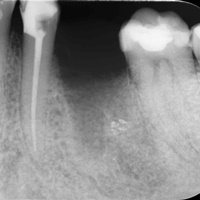

Wybielanie obejmujące pojedyncze zęby jest dość często spotykane. Najczęstszą przyczyną dyskoloracji zęba jest obumarcie miazgi i brak następowego poprawnego leczenia kanałowego, lub leczenie nieprawidłowe. Czasami udaje się przeprowadzić proces wybielania, który jest zadowalający dla pacjenta, a czasami w oparciu o uzyskany wynik można przeprowadzić leczenie protetyczne np. koroną lub licówką całoceramiczną.

Trzeba jednak uważać, ponieważ nieumiejętnie przeprowadzone wybielanie może być przyczyną resorpcji wewnętrznej i może sie skończyć utratą całego zęba...juz wybielonego. Poniżej zdjęcia przed i po leczeniu mikrochirurgicznym resorpcji.